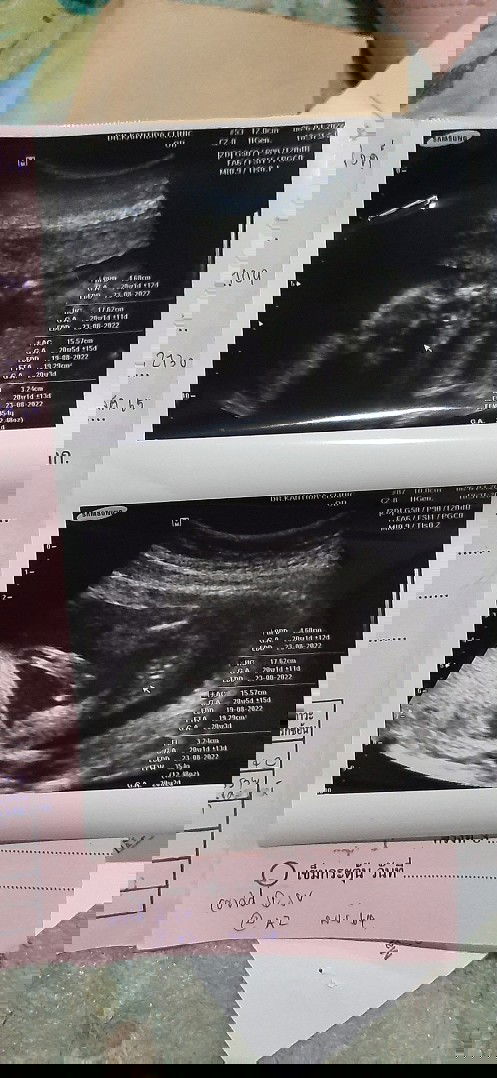

พอดีบ้านนี้ท้องได้16วีคแล้วค่ะ มีแต่คนทักว่าท้องไม่ออกเลย #ท้อง2แล้วค่ะ แต่พอไปซาวเมื่อวันเสาร์ที่ผ่านมาคุณหมอบอกน้องตัวโตดี นน.128กรัม ความยาวเท่าไรไม่ทราบค่ะ ถือว่ากำลังดีใช่ไหมคะแม่ๆ โดนทักบ่อยมากว่าสรุปมีเด็กอยู่ในท้องไหมเนี้ย🥺